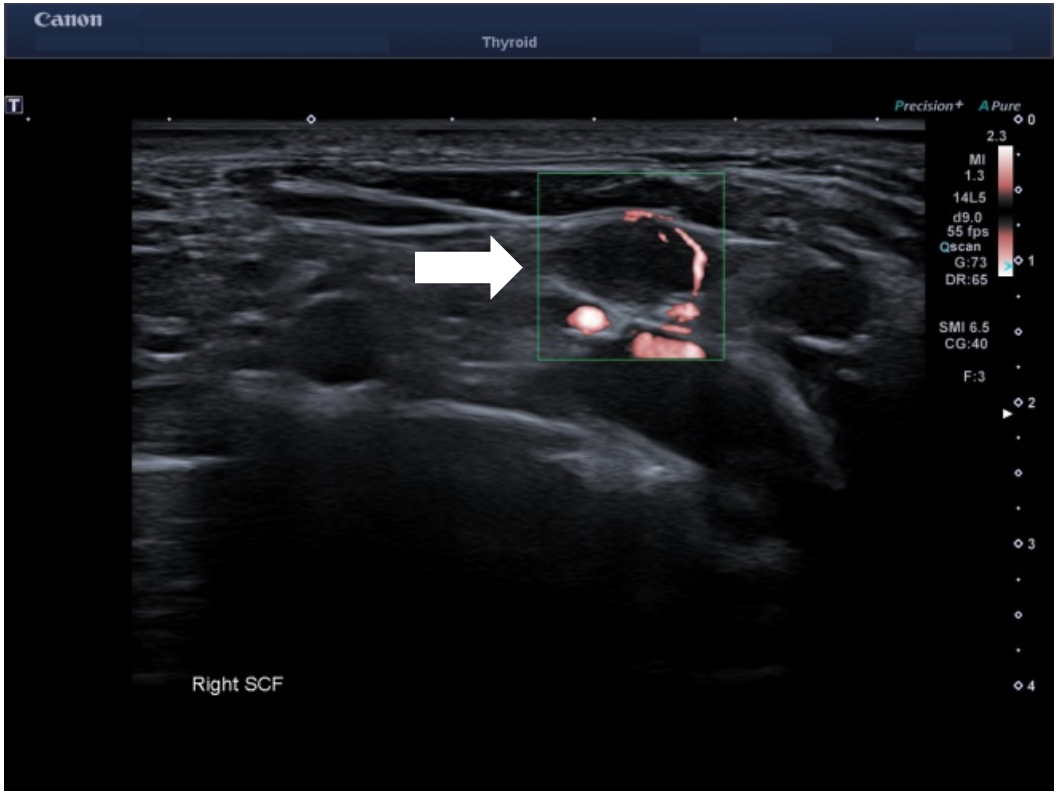

Owing to the aggressive cancer in a young patient, a staging PET/CT study was performed which showed a small but metabolically active lymph node in the right supraclavicular fossa. An US of the supraclavicular fossa revealed several small volume nodes. The most prominent 10 x 4 mm node had a normal architecture but with only mild cortical thickening. Power Doppler imaging (PDI) and color Doppler imaging (CDI) showed feeding vessels but otherwise no suspicious features. However, on using Superb Microvascular Imaging monochrome (SMI), this revealed abnormal peripheral vascularity which was best depicted in the monochrome mode. This feature made the node suspicious for malignancy and corresponded to the FDG avid node on the PET study. Subsequent fine needle aspirate of the right supraclavicular node confirmed metastatic disease.

Longitudinal ultrasound of right supraclavicular fossa showed a small 10 x 4 mm lymph node in the right supraclavicular fossa (SCF) with mild cortical thickening. SMI revealed abnormal peripheral vascularity which made it suspicious for metastatic infiltration and most likely represented the metabolically active SCF node on the recent PET imaging.

Background: There are a growing number of clinical applications using SMI to evaluate diseases closely associated with angiogenesis, including evaluating lesions in liver, breast, thyroid and skeletal muscle. SMI separates flow from overlaying tissue motion preserving subtle low-flow components which gives improved detail and definition compared to PDI and CDI. The SMI monochrome mode removes anatomical background information and reveals fine vasculature with high sensitivity. SMI has recently been shown to be more effective in assessing breast and thyroid lesions than PDI and CDI. It may offer a safe and low-cost alternative to Contrast Enhanced Ultrasound (CEUS).

Clinical perspective: PDI and CDI ultrasound showed relatively normal vascularity in the SCF Lymph node, however, SMI, particularly monochrome mode, outlined clearly the abnormal peripheral vascularity which allowed FNA of the correct “small” node which was FDG avid on the PET study . A recent study has shown SMI yields more detailed information about nodal vessel when compared to PDUS and can be useful in differentiating between malignant and benign lymph nodes.